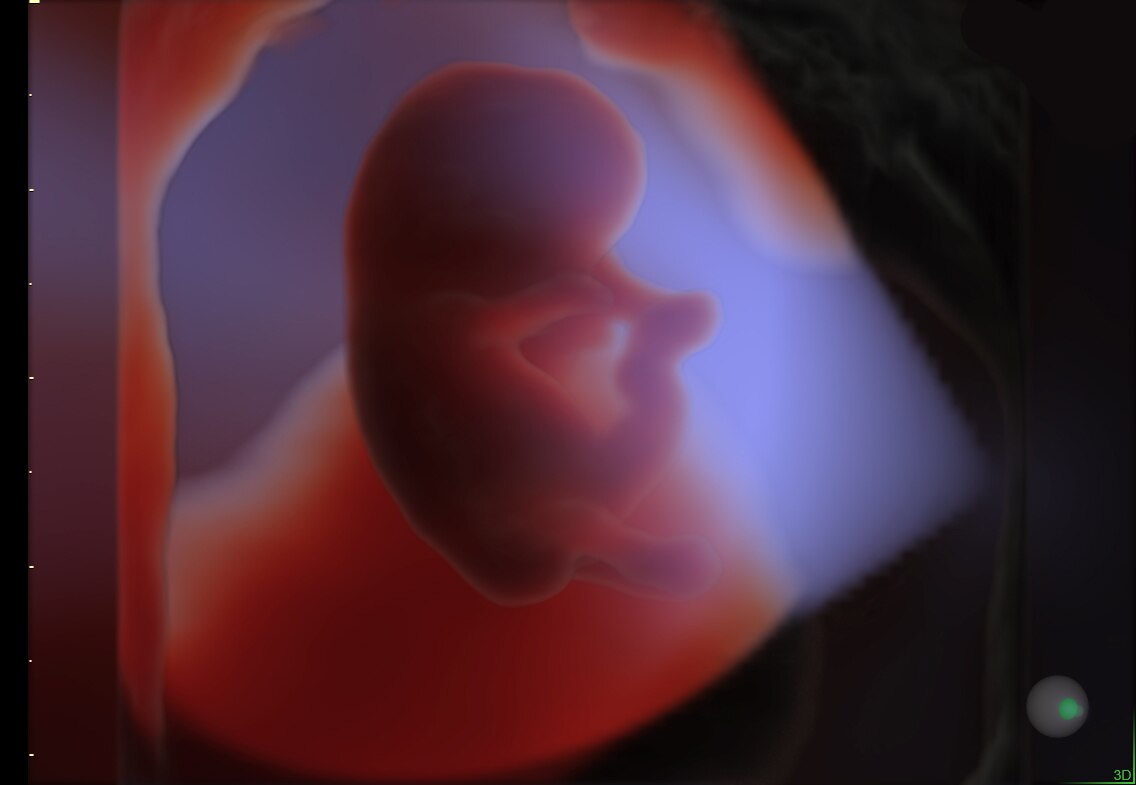

HDlive Studio on a 10-week fetus